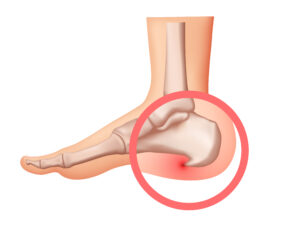

Plantar Fasciitis: Causes, Symptoms, Diagnosis, and Effective Treatments

Introduction Plantar fasciitis is a common cause of heel pain. Many people feel sharp pain in their heel, especially in the morning. This condition happens